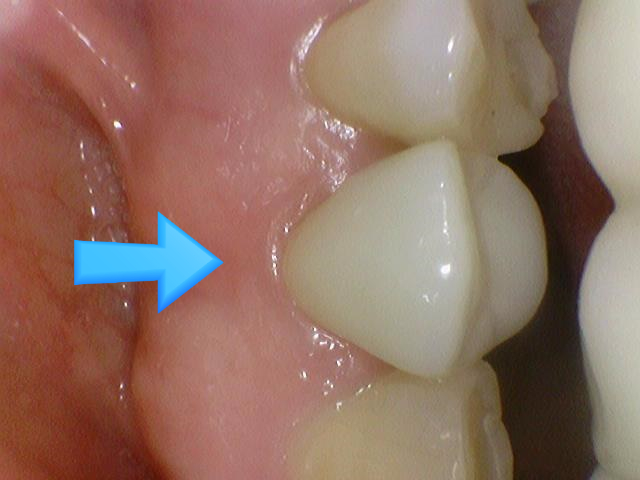

깨진 치아를 지르코니아 크라운으로 치료

위 케이스 지르코니아 크라운을 옆에서 본 사진 ↓